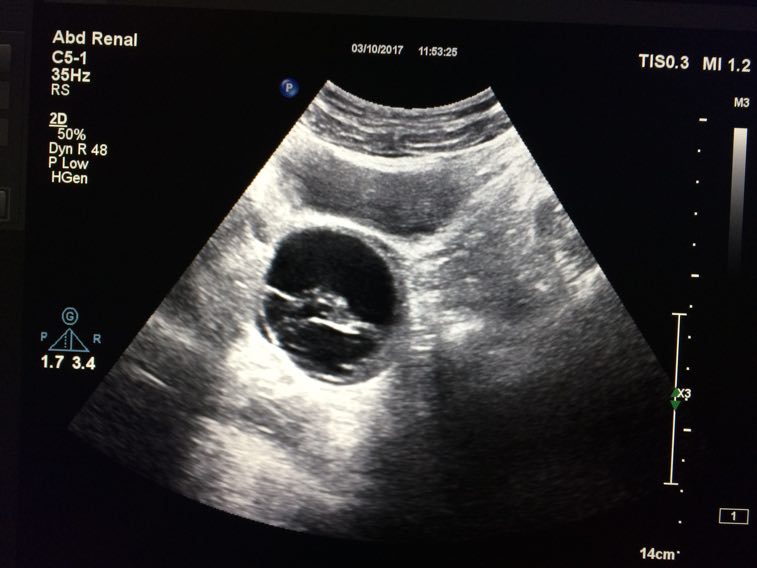

卵巢囊肿

月经前一天做彩超示:右侧卵巢囊肿大小约为56×44mm ,乳腺增生。症状:月经推后十天,量少,色暗黑红,质稠,夹血块多。纳可眠可,大便不成型,小便正常。无痛经,无乳房胀痛,无腰酸,不怕冷。舌苔白腻,脉?囊肿经验方或者常用中药?